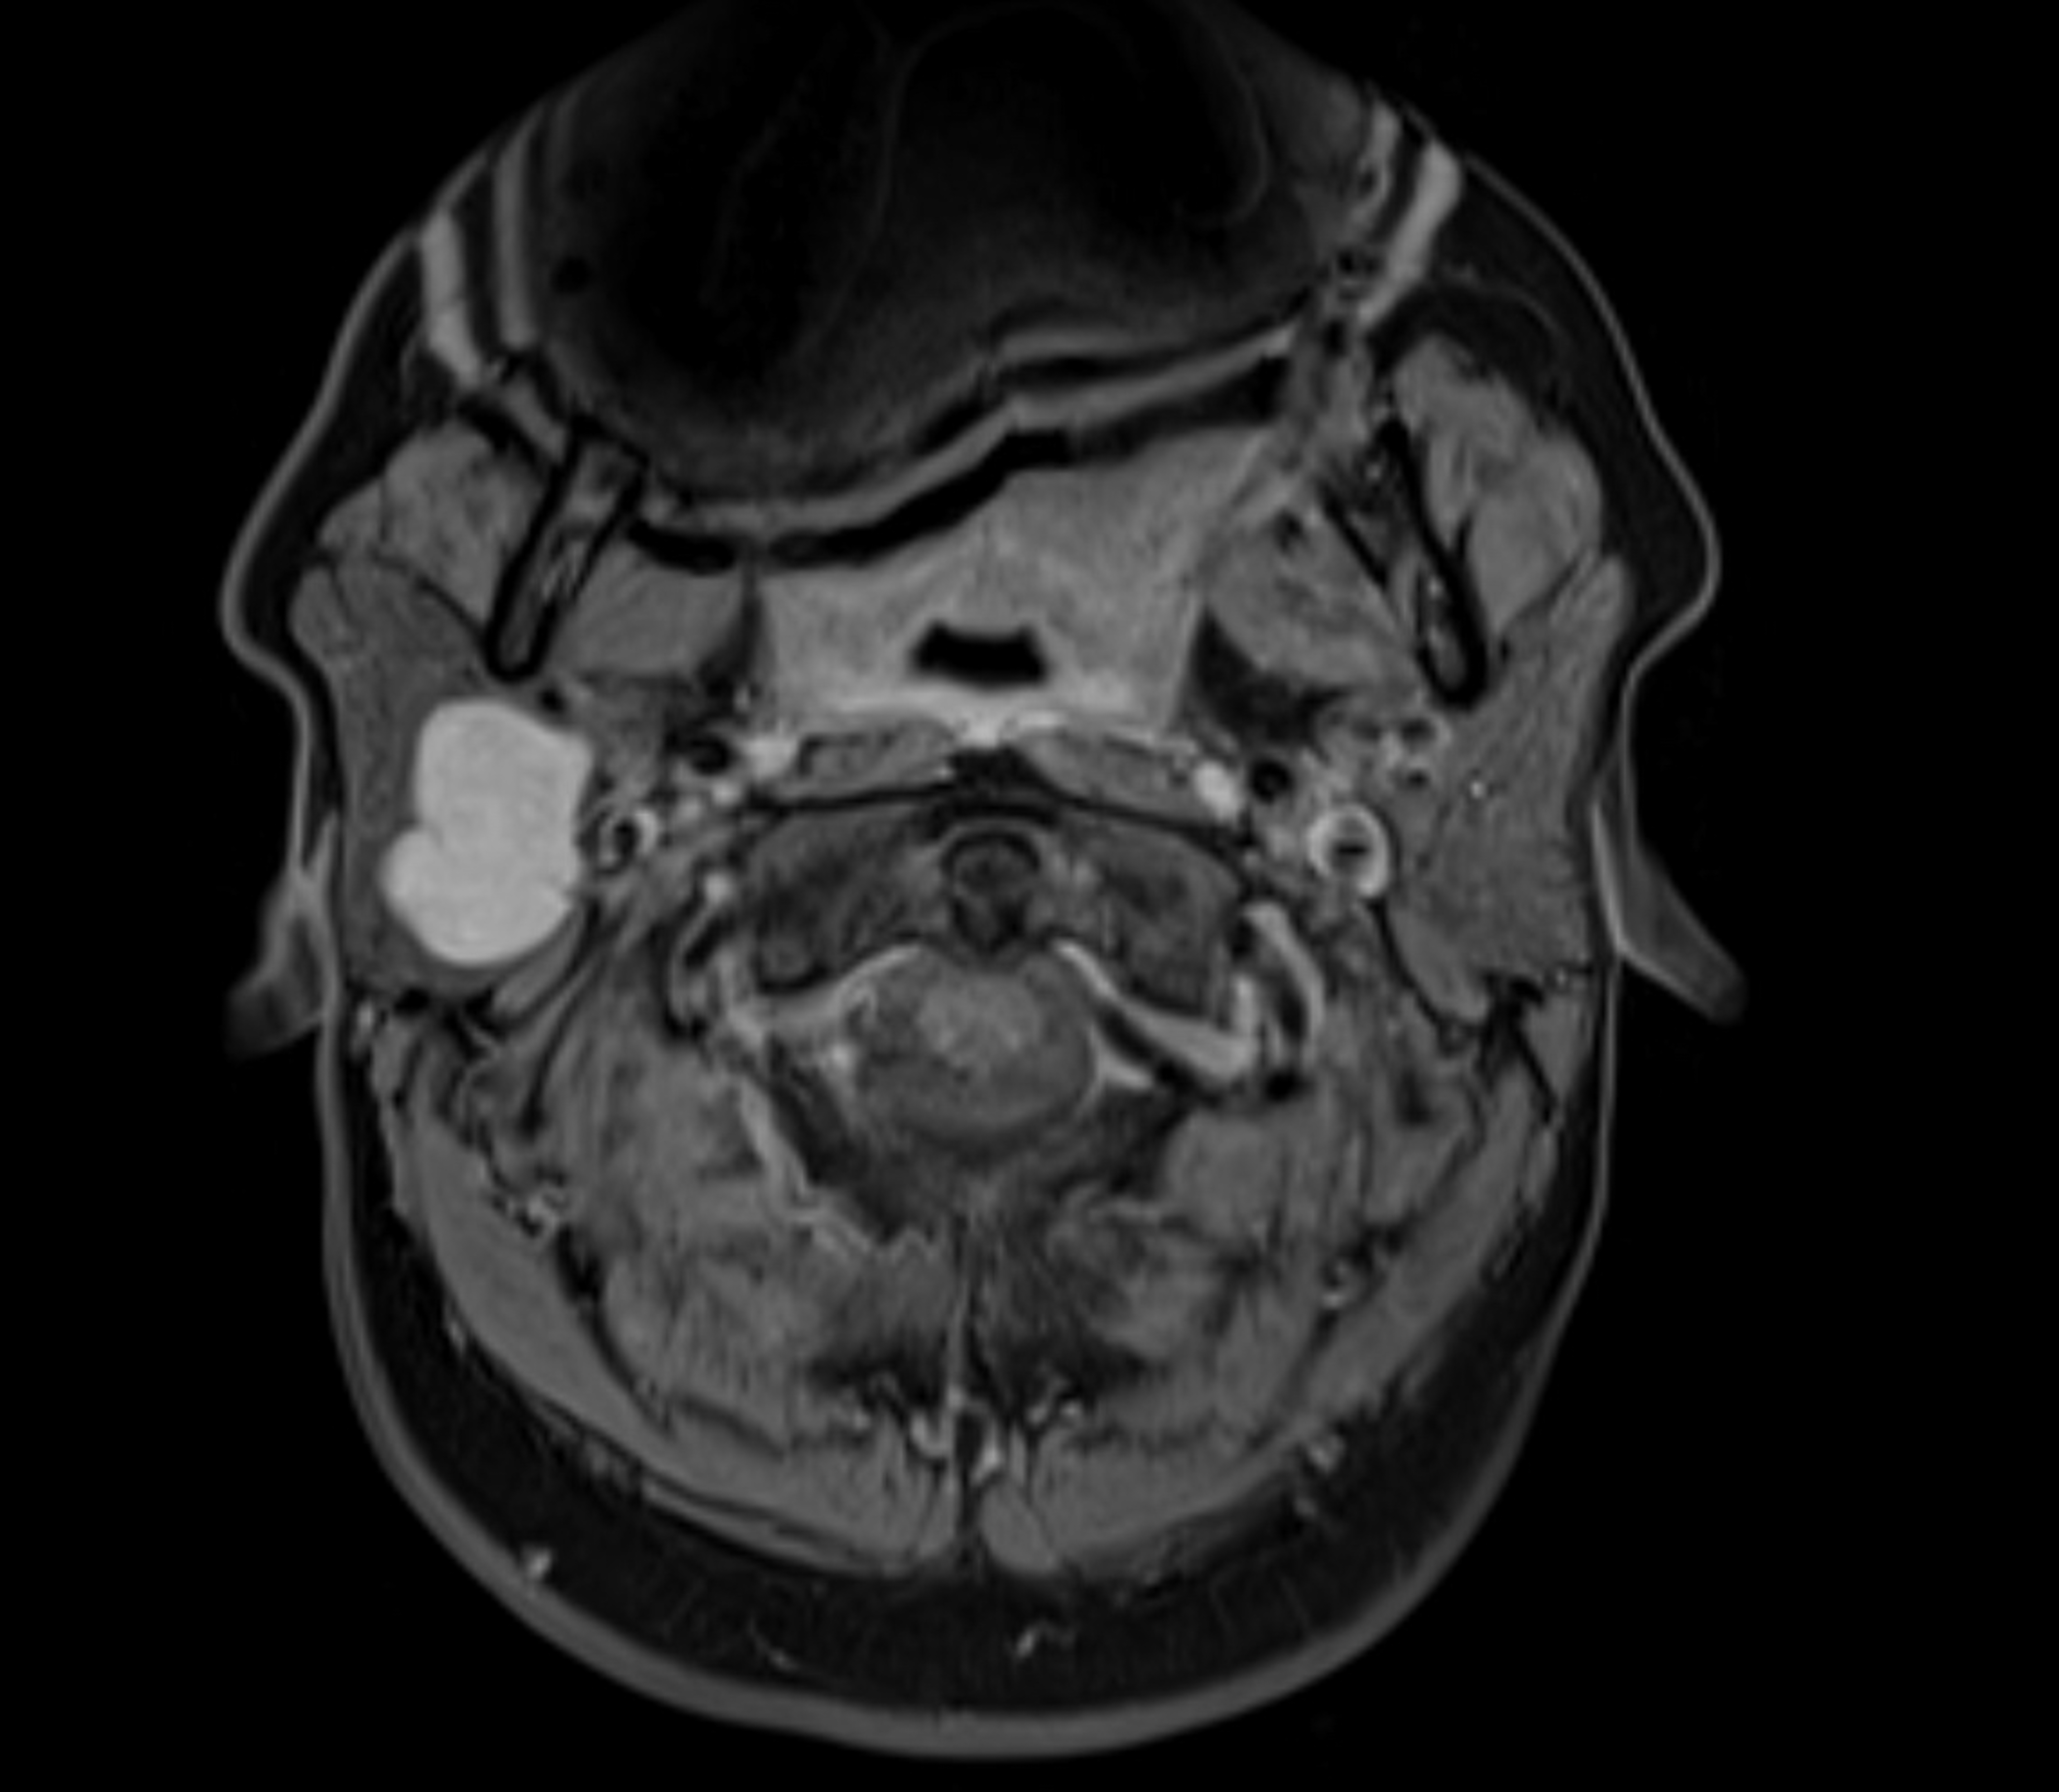

Resonancia magnética axial multiparamétrica que muestra un tumor de la glándula parótida | Fuente: Getty Images